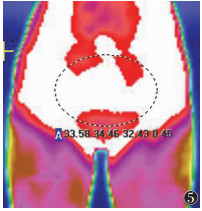

服用温经汤1个疗程后,子宫及宫颈区细胞代谢热明显较前增加,热断层过程中与腹股沟淋巴迅速连成一片;下腹部及腰骶部向上的脊柱可见竖条状细胞代谢热增加,呈上升趋势,热辐射值均明显高于用药前(均P < 0.05)(图 4~6)。

| 图 6 女,23岁,原发性寒湿凝滞型痛经,下腹部及腰骶部向上的脊柱可见竖条状细胞代谢热增加,呈上升趋势 |